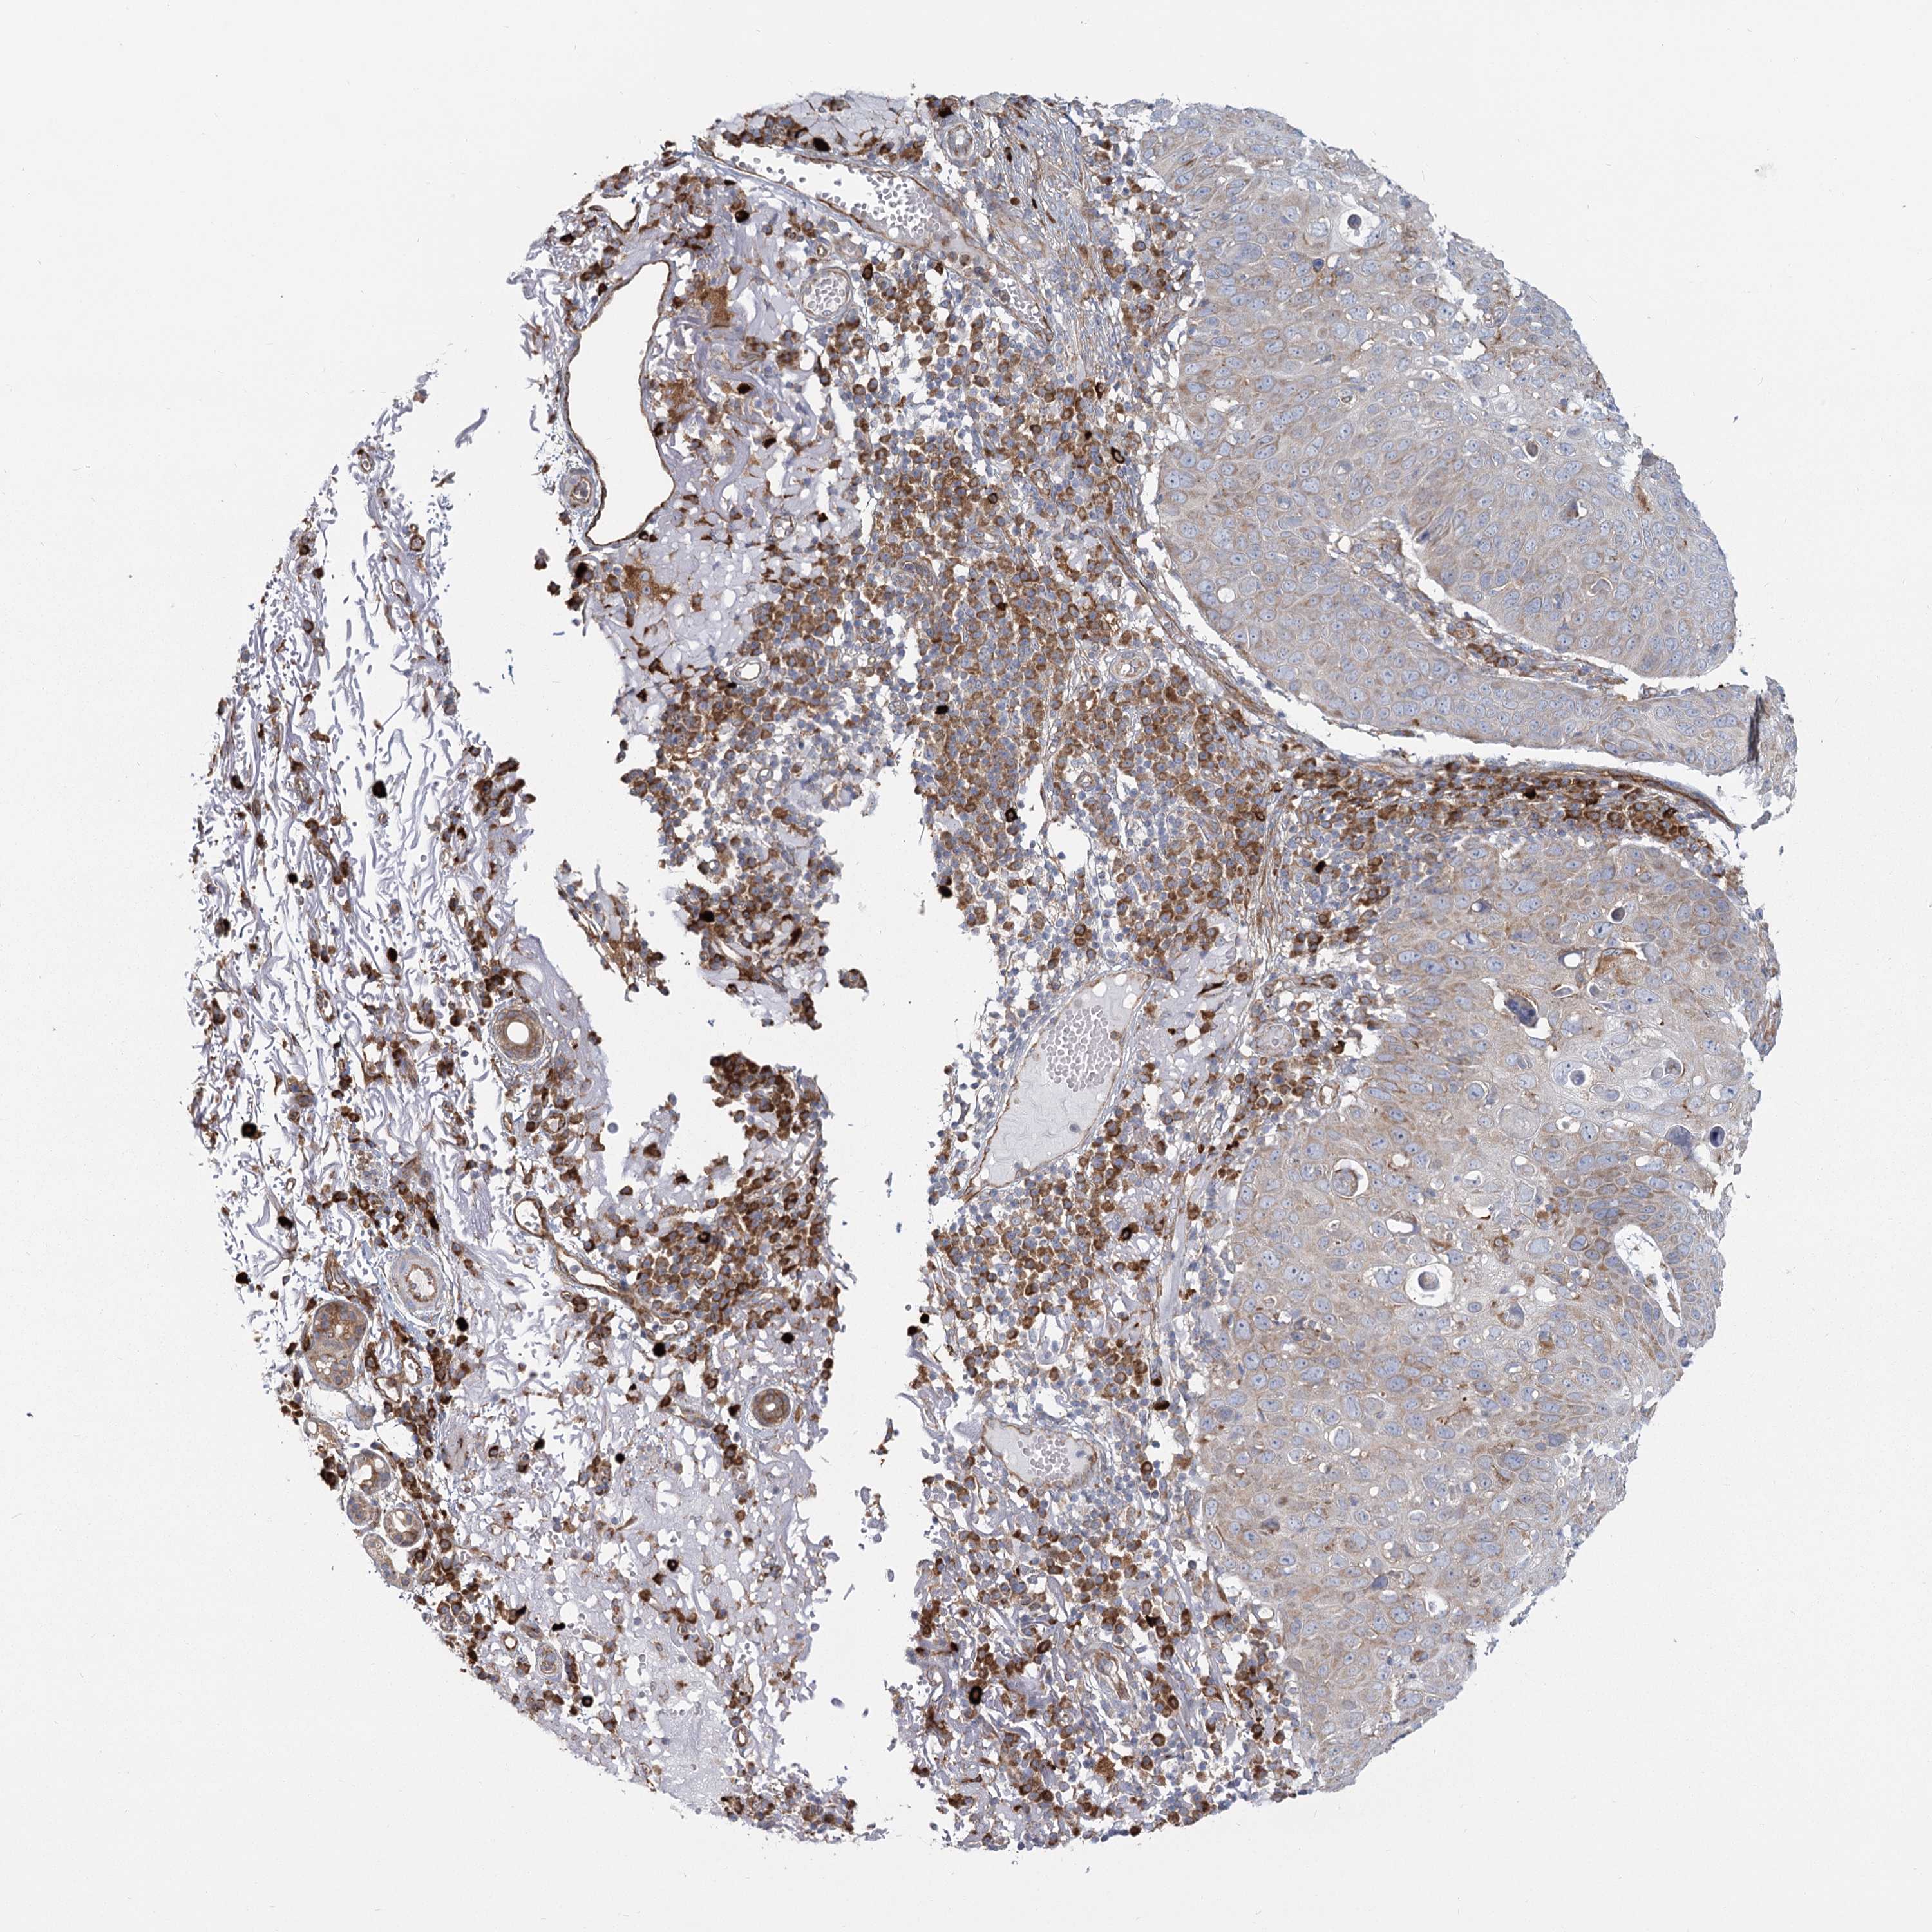

Basal cell and squamous cell cancer

SKIN CANCER - Protein expressioni

A mouse-over function shows sample information and annotation data. Click on an image to view it in a full screen mode. Samples can be filtered based on level of antibody staining by selecting one or several of the following categories: high, medium, low and not detected. The assay and annotation is described here.

Antibody stainingi

Antibody staining in the annotated cell types in the current human tissue is reported as not detected, low, medium, or high, based on conventional immunohistochemistry profiling in selected tissues. This score is based on the combination of the staining intensity and fraction of stained cells.

Each image is clickable and will lead to virtual microscopy that enables deeper exploration of all samples and also displays staining intensity scores, fraction scores and subcellular localization as well as patient and tissue information for each sample.

Antibody HPA035941

Squamous cell carcinoma, metastatic, NOS

Squamous cell carcinoma, NOS